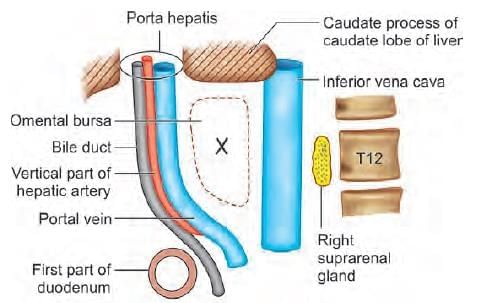

Superior boundary of the arrow marked structure is: (INI-CET July 2021)

Liver is divided into eight segments according to Couinaud’s classification based upon. (AIIMS May 2019)